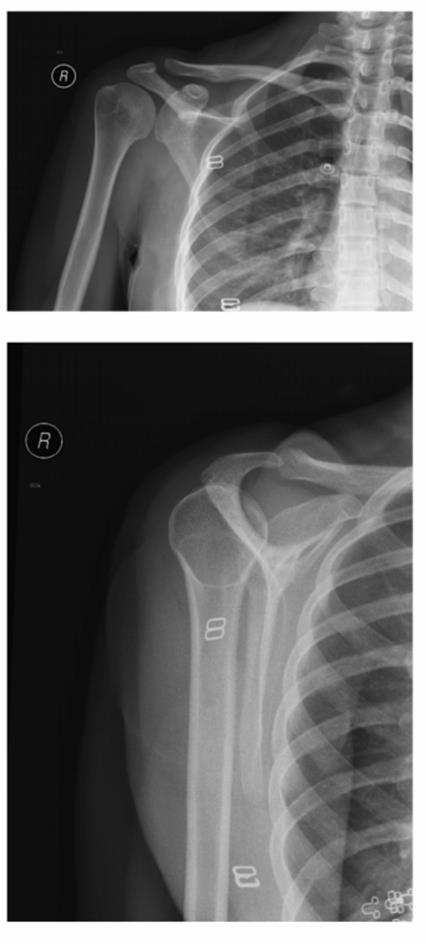

o Perform an AP (Figure 2.1A) and a lateral projection (axillary lateral or scapular Y-view) (Figure 2.1B)

Figure 2.1A and 2.1B Radiographs of a posterior shoulder dislocation.

A: An AP projection is shown with no obvious dislocation.

B: A lateral projection (scapular Y-view) for the same patient shows the humeral head to be dislocated posteriorly. (Reproduced with permission of the Department of Emergency Medicine, Feinberg School of Medicine, Northwestern University.)